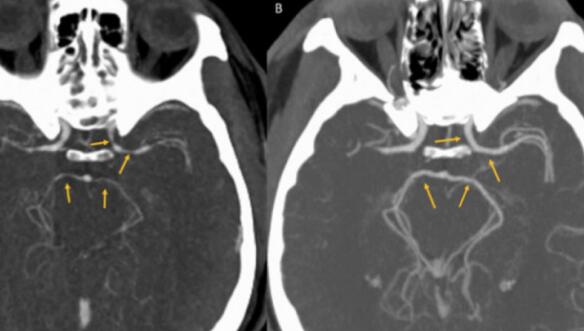

各种神经系统问题的检测结果都呈阴性,但CT扫描发现,该男子大脑中的动脉受压。因此神经病学家格雷戈里·卡明斯医生诊断他得了霹雳性头痛 (thunderclap headaches)。这是一种少见的极端性头痛,病人感觉就好像是被霹雳击中。该男子的霹雳性头痛是由可逆的脑血管收缩综合征引起的,这是一种暂时性的大脑动脉收缩。

经过静脉输液以及止痛药物治疗之后,该男子身体康复。在五周内,他的动脉恢复了正常。